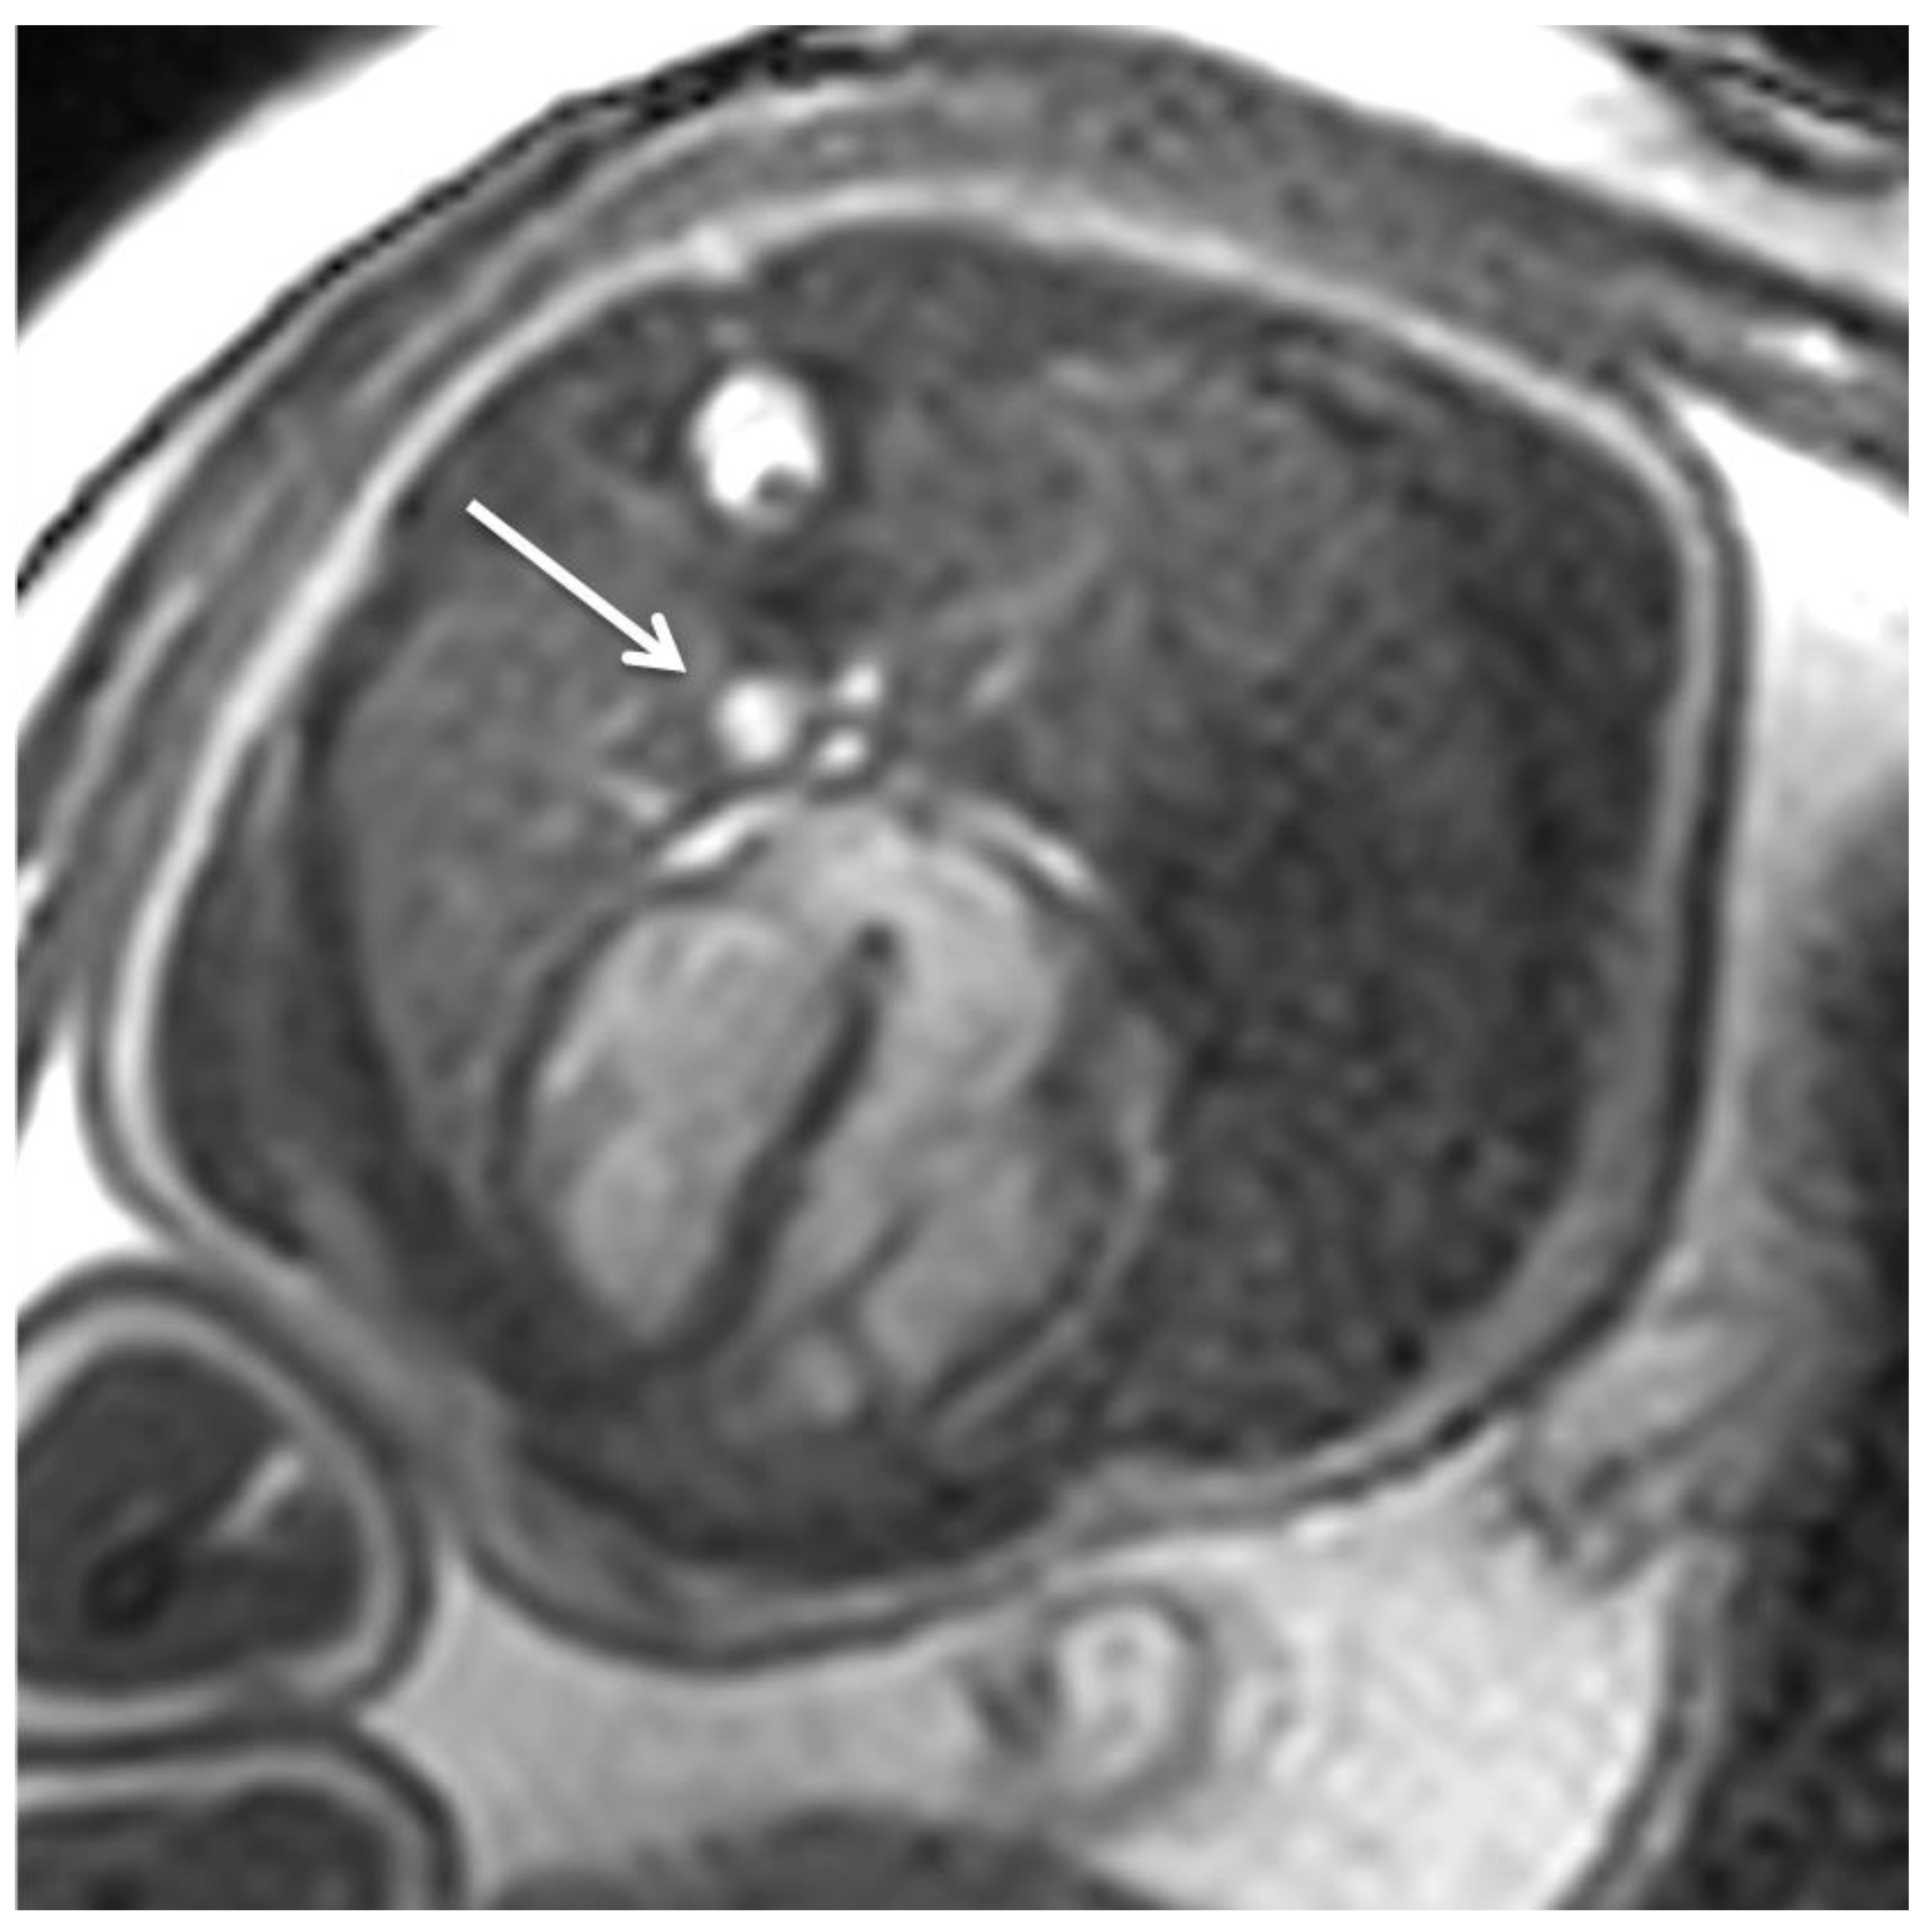

The Evolution and Developing Importance of Fetal Magnetic Resonance Imaging in the Diagnosis of Congenital Cardiac Anomalies: A Systematic Review

2. Fetal Cardiac MRI Techniques

3. Current Potential and Clinical Application of Fetal Cardiac MRI